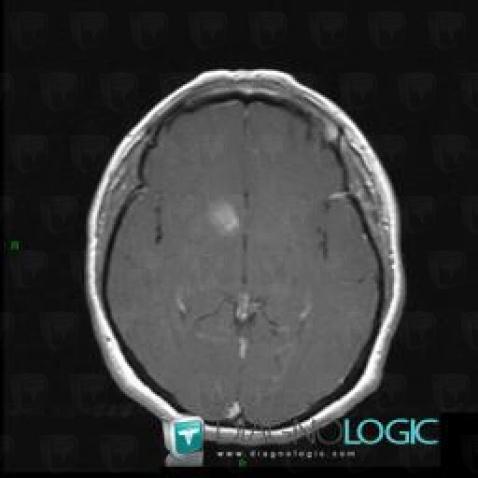

Télangiectasie capillaire, Hémisphères cérébraux, Noyaux gris centraux et capsule, IRM

Voici les informations spécifiques à l'image clé ci dessus:

- Diagnostic Télangiectasie capillaire, Localisation(s) Hémisphères cérébraux, comportant les gammes Lésion intracérébrale à réhaussement modéréNoyaux gris centraux et capsule, comportant les gammes